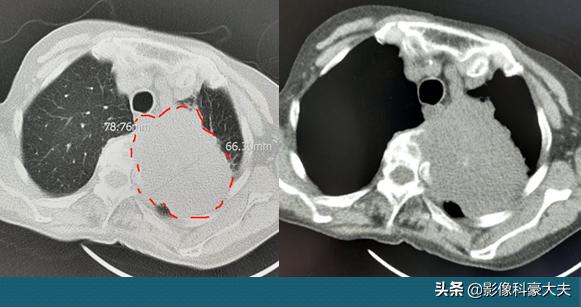

这位老人82岁,女性,抽烟65年,每年3斤。左边肩背部疼痛3个月,以为是上了年纪,颈椎病肩周炎了,开始吃点止疼药能缓解,最近十多天疼得厉害了。

肺部CT发现左侧肺癌,7.8×6.6cm大小的肿瘤,她的肩周炎症状是癌细胞破坏胸膜和胸椎造成的,晚期了……

贴近胸膜的早期肺癌,或者肿瘤较大侵犯胸壁破坏神经,有时可以出现类似肩周炎的症状,吃止疼药可以缓解。但对于中老年人近期出现的肩背痛,不建议自行购买舒筋活络的止疼药胡乱对付,尽量挂骨科先看看,简单排查一下早期肿瘤再对症治疗。